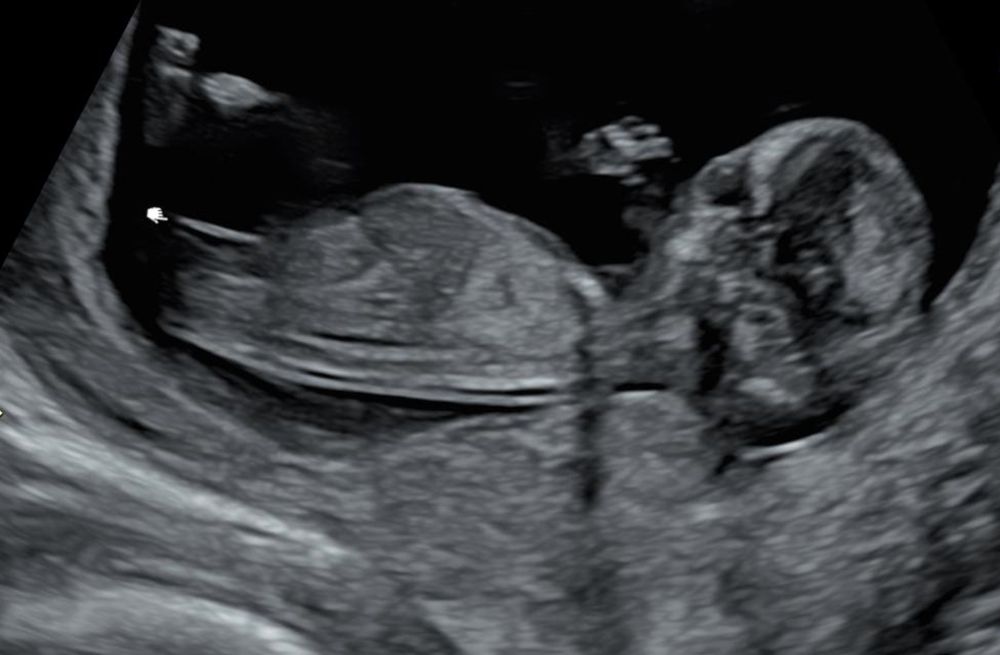

А по УЗИ сказали, что скорей всего девочка. Срок был на УЗИ 12 недель и 4 дня. Я рассмотрела снимки УЗИ и, мне кажется, это девочка 100%. А вам как кажется? Первый снимок чуть жутковатый, добавила второй просто так, красивый профиль)

На первом фото малыш сосет пальчик вроде)) Мне тоже похоже на девочку. У меня тоже такая полосочка на фото в 12 недель в дневнике))

Алена, на первом фото он не сосет пальчик, т.к. лицо повернуто к нам. У вас точно девочка, несколько фото и горизонтальный бугорок. У меня только одно фото в таком ракурсе, где там что-то видно, узистка с большим опытом, не сказала однозначно, поэтому есть микронадежда на мальчика. Это моя первая беременность, поздняя, еще поэтому так тревожно.